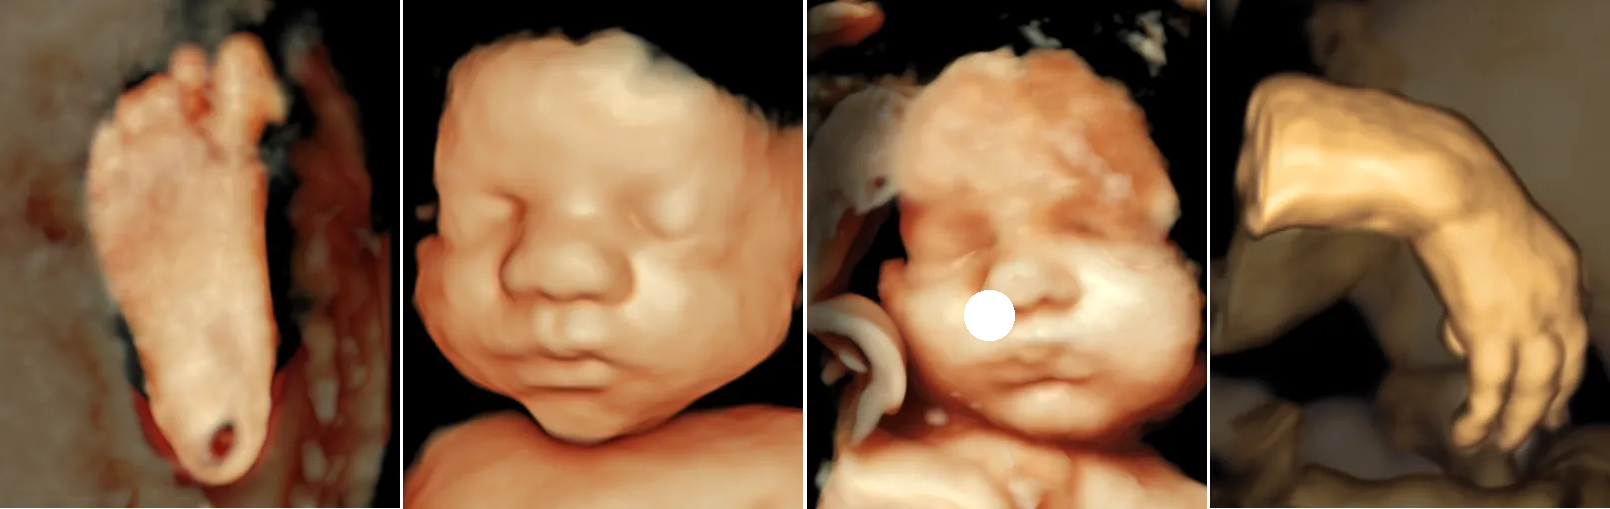

Prenatal ultrasounds (from left) of a foot at 25 weeks, a face at 33 weeks, a face at 34 weeks, and a hand at 23 weeks.

At the Fetal Care and Surgery Center, we perform prenatal ultrasounds using state-of-the-art equipment. This advanced technology allows us to obtain incredibly detailed 2D and 3D images of the smallest structures, examine blood flow, and provide a comprehensive view for patients and their doctors.